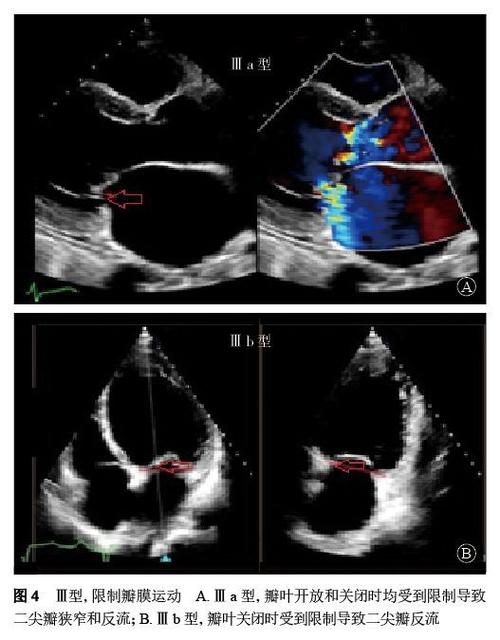

点击查看大图 图1 二维simpson法(图1a)与三维超声心动图测量的左